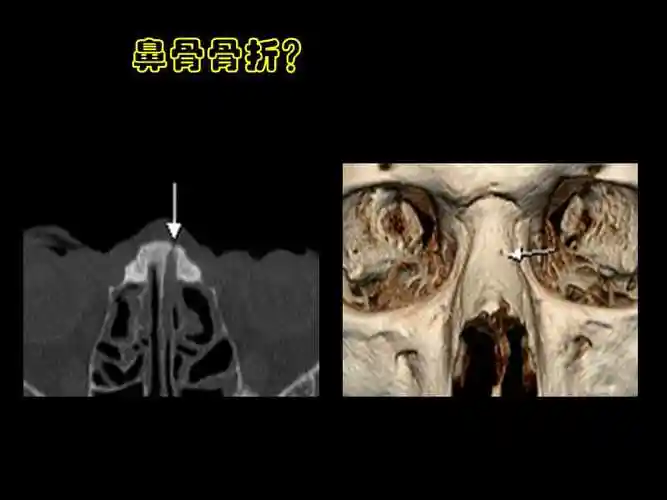

鼻骨与副鼻窦解剖ppt课件ppt